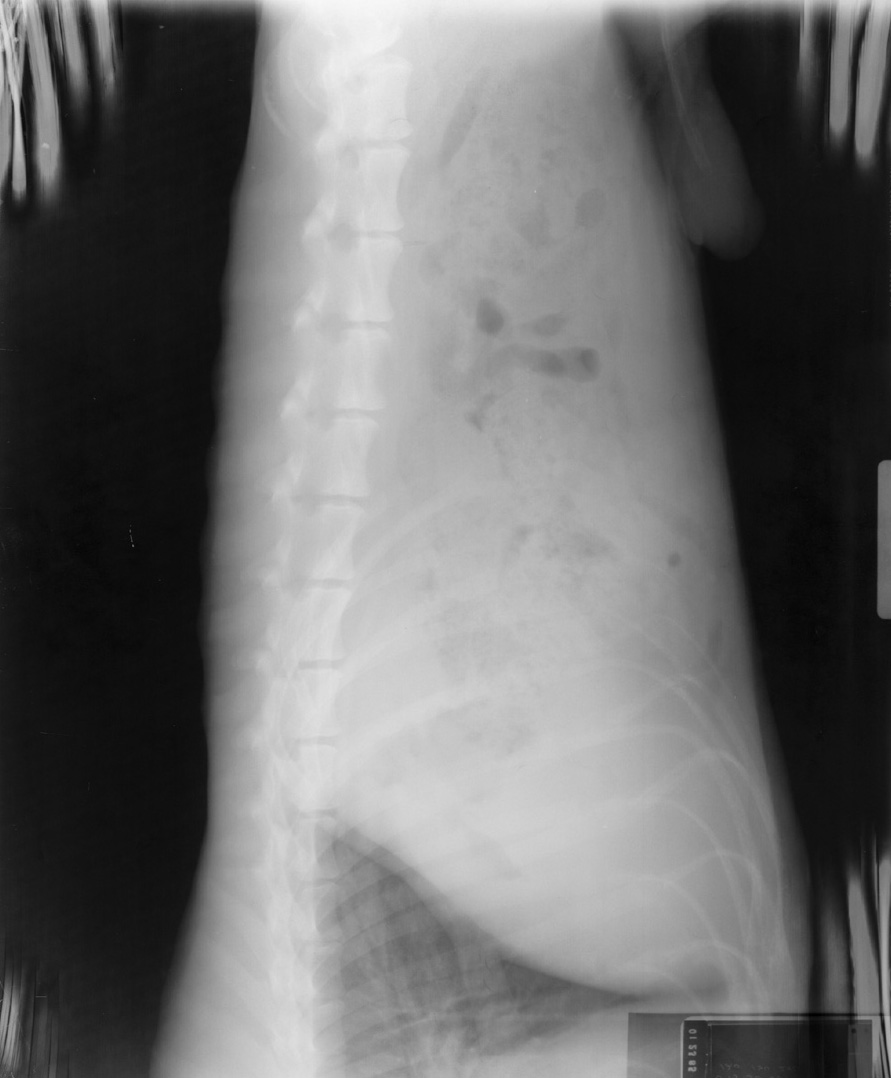

Stuck in Processor

See grid lines.